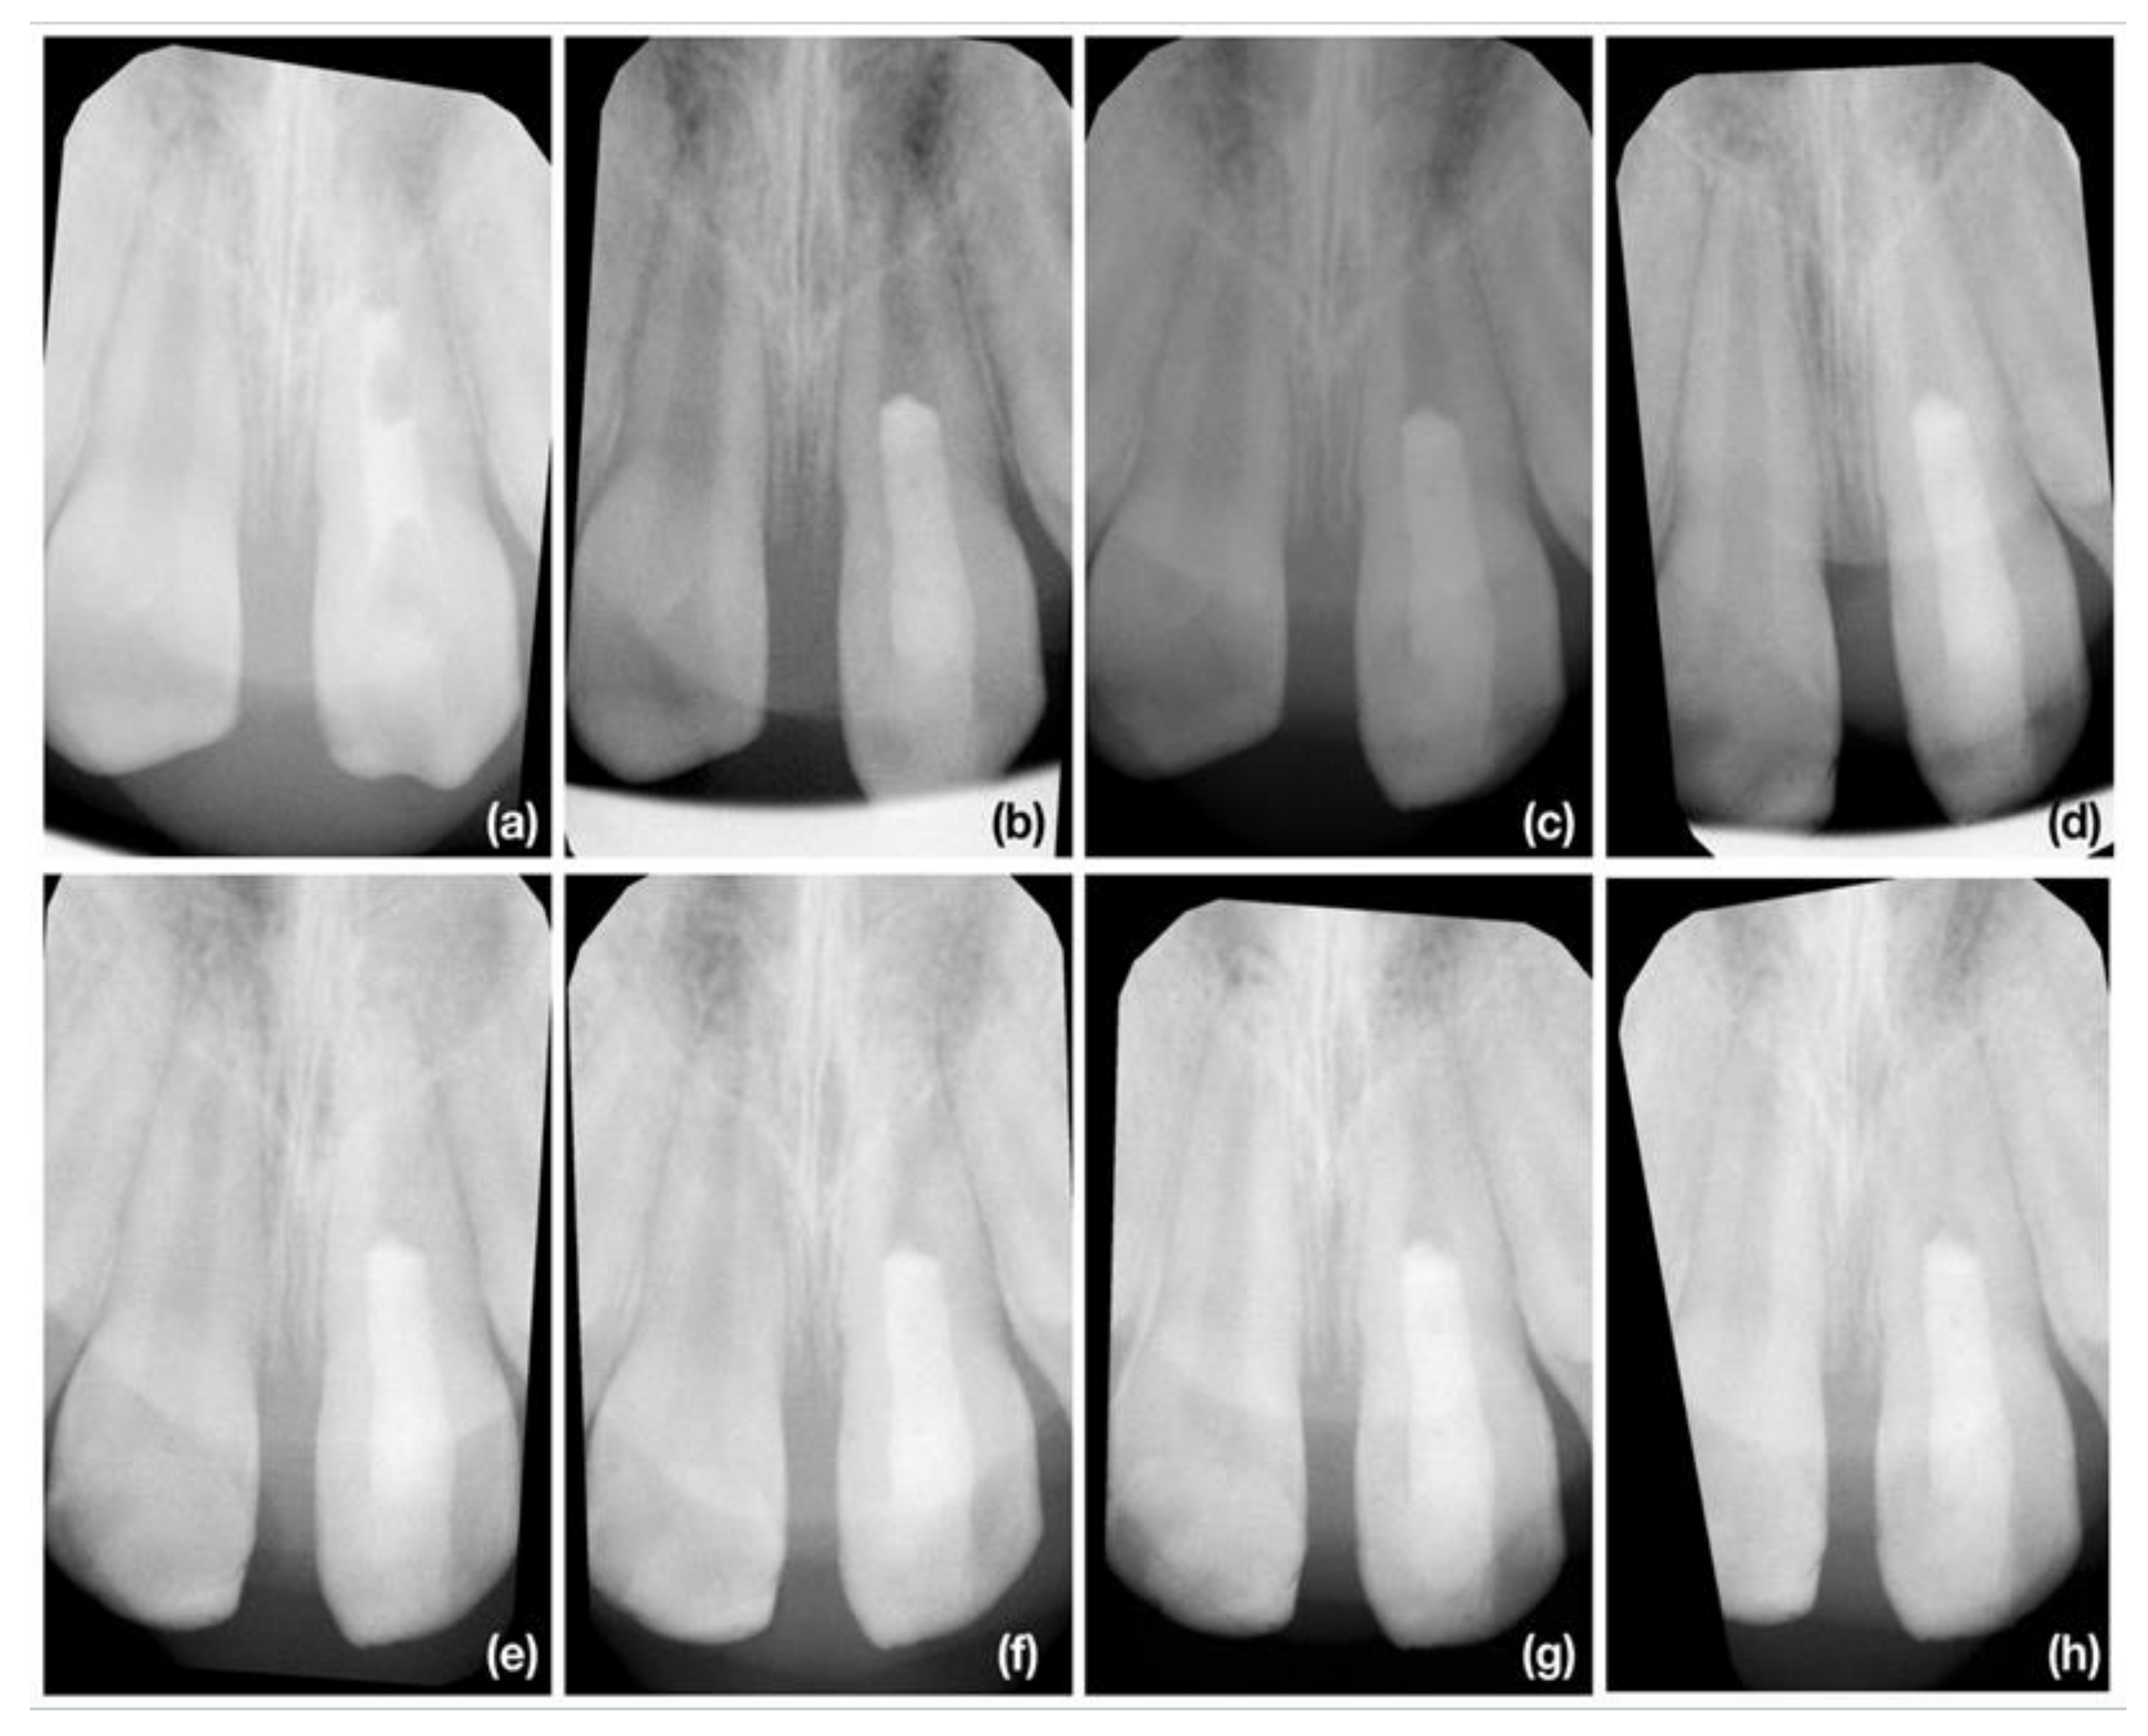

3.2. Radiographic Root Length Change

3.3. Radiographic Root Width Change

3.4. Radiographic Root Area Change